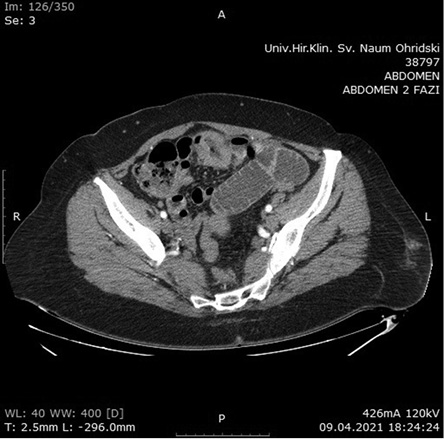

The patient was referred to a hematologist for proper staging and therapy. The positron emission tomography-computed tomography (PET/CT) scan showed a normal findings with low metabolic activity in the area of the wound infection (Figure 4). Bone marrow biopsy was negative. According to the Lugano score [7], the patient was diagnosed with Stage I of the disease.

Seven cycles of R-CHOP (rituximab, cyclophosphamide, doxorubicin, vincristine, and prednisolone) regimen were given to the patient as the first line of treatment. Post-chemotherapy PET/CT scan presented with normal findings. The patient is still in complete remission after the combined treatment with surgery and chemotherapy and regular future checkups are scheduled.

Figure 4. PET/CT scan with normal finding